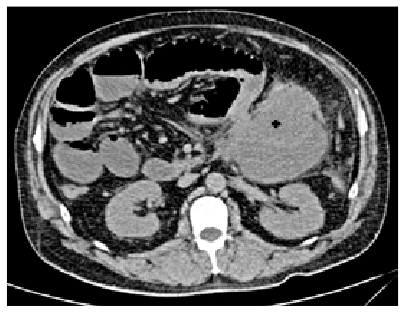

Paciente masculino de 57 años, sin antecedentes familiares de cáncer, que inició su cuadro siete días antes de su ingreso, con dolor abdominal de inicio súbito en cuadrantes abdominales superiores, referido de carácter difuso y de intensidad moderada, tipo cólico, puntuado 7/10 en la escala numérica verbal, que se acompaña de náuseas sin desencadenar vómito, niega fiebre, diarrea o algún otro antecedente relevante, el paciente evoluciona con aumento progresivo del dolor y presencia de escalofríos, motivo por el cual acude a evaluación hospitalaria. En la exploración física se encuentra con presión arterial de 125/75 mmHg, frecuencia cardíaca de 105 lpm, 20 respiraciones por minuto, temperatura de 36.5 °C, abdomen semigloboso, ausencia de peristalsis, con dolor a la palpación superficial y profunda generalizado, con predominio en mesogastrio, resistencia involuntaria, con signo de descompresión positiva. El resto del examen general sin alteraciones. El análisis de sangre de urgencias mostró glucosa 209 mg/dL, creatinina 0.97 mg/dL, proteína total 4 gr/dL, albúmina 2 gr/dL, fosfatasa alcalina 49.8 UI, deshidrogenasa láctica 204 UI, bilirrubina total 1.4 mg/dL, bilirrubina directa 1.08 mg/dL, bilirrubina indirecta 0.32 mg/dL, sodio 140 mmol/L, potasio 3.9 mmol/L, hemoglobina 14.2 gr/dL, hematocrito 45.4%, glóbulos blancos 11.4 k/uL, plaquetas 231 k/uL, TP 17, TPT 24.7, INR 1.33, Se realiza una tomografía computarizada (TC) simple, que muestra una imagen ovoide con bordes regulares y bien definidos de 113 x 89 x 104 mm con contenido heterogéneo en la región inferior del páncreas y anterior al riñón izquierdo. No fue posible identificar la dependencia de órganos del tumor (figuras 1 y 2).

La tomografía axial computarizada muestra lesión tumoral en colon transverso (cruz negra)

La tomografía computarizada corte coronal muestra lesión tumoral en colon trasverso (cruz negra)